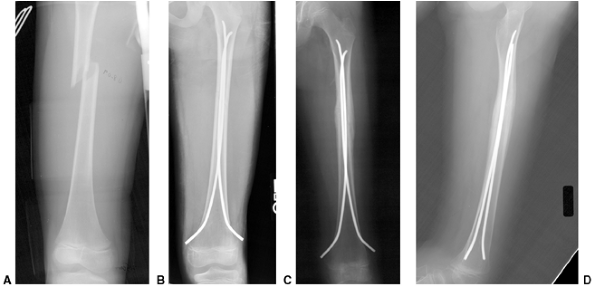

![]() |

|

Figure 33.3 Distal tibial growth arrest. A: Distal tibial physeal Salter-Harris type IV injury treated with cast immobilization without reduction. B:

Two years later, there is varus angulation to the distal tibia from a medial physeal bar. The Harris growth arrest line is not parallel to the distal physis, and does not extend across the entire width of the metaphysis. |